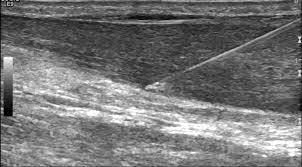

High volume injection stripping

Πρόκειται για ιδιαίτερα φιλικές κι ακίνδυνες θεραπείες, οι οποίες γίνονται με υπερηχογραφική καθοδήγηση

με σκοπό την ενίσχυση της επουλωτικής διεργασίας του οργανισμού του ασθενούς.